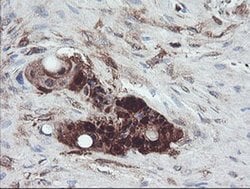

TSC22D1 Monoclonal Antibody (OTI1A5), Invitrogen™

Supplier: Thermo Scientific MA526037

TSC22 domain family protein, or TSC22, is a transcription factor that belongs to the large family of early response genes. This transcriptional repressor is known to act on the C-type natriuretic peptide (CNP) promoter. TSC22 belongs to the TSC-22/Dip/Bun family and is an intracellular protein that may be found in the cytoplasm or nucleus. This transcription factor is known to regulate cell growth, differentiation and cell death and is involved in modulating the transcriptional activity of Smad3 and Smad4. This protein is ubiquitously expressed in most tissues and widely in both fetal and adult tissues. It is generally expressed in aortic endothelial cells, and induced by cytokines, including TGFB. These proteins may be possible therapeutic targets of leukemia and prostate cancer.

| Immunohistochemistry (Paraffin), Western Blot | |